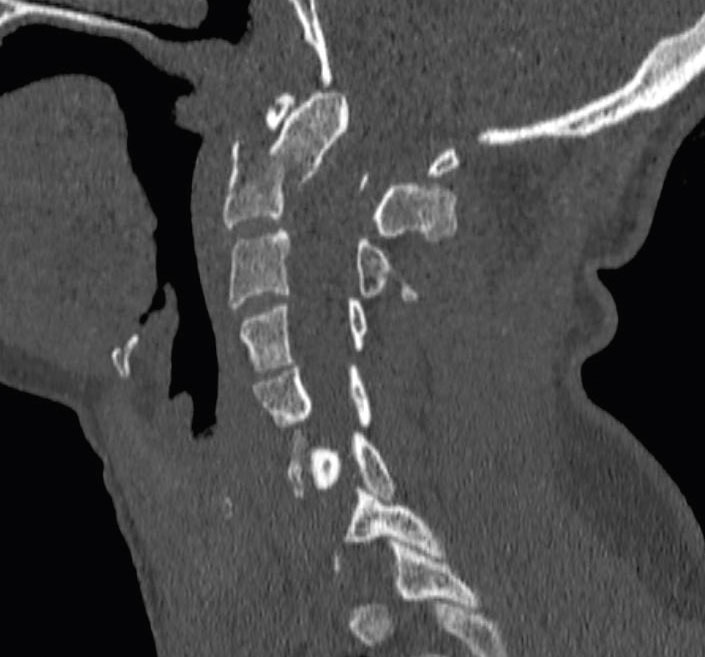

Datortomografi av traumatisk densfraktur med dislokation, typ 2.